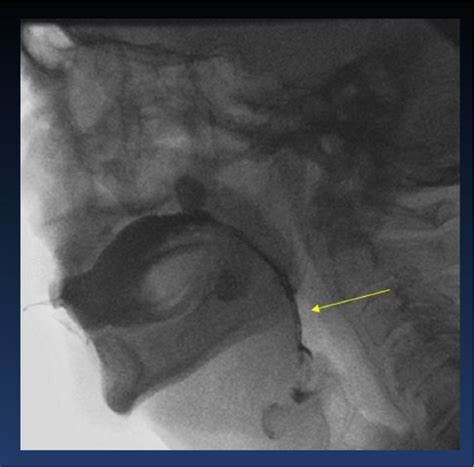

The Videofluoroscopic Swallow Study (VFSS), also known as a modified barium swallow, is a diagnostic procedure that uses fluoroscopy and a barium-based contrast material to visualize the swallowing process. This study helps identify the specific phase of swallowing that is impaired, whether it is the oral, pharyngeal, or esophageal phase.

The results of a Videofluoroscopic Swallow Study provide valuable information about the swallowing process. The healthcare team looks for various indicators, including:

• Aspiration: The entry of food or liquid into the airway, which can lead to pneumonia.

• Penetration: The entry of food or liquid into the laryngeal vestibule but not below the vocal folds.

• Residue: The remaining food or liquid in the mouth, pharynx, or esophagus after swallowing.